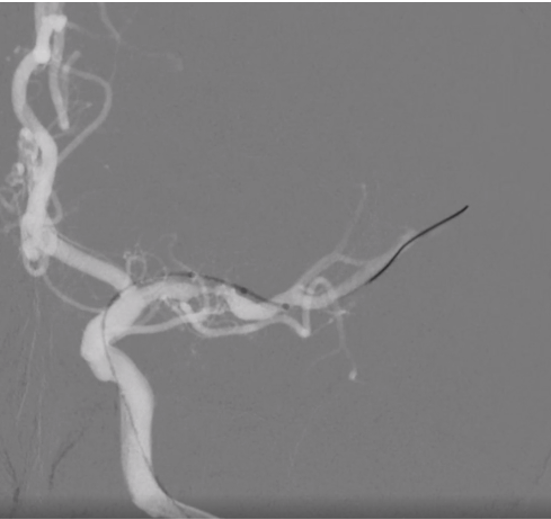

咱们来举几个病例,来详细说说它的优点,第一、定位准确,无需导丝交换,以一例左侧大脑中动脉狭窄为例(见病例1)。

微导丝配合球囊顺利通过狭窄,到达大脑中动脉M2段,无需导丝行走过远,球囊可以轻松到位(病例1B)

随后常规球囊6ATM扩张,复查造影满意后,释放4.0*23无Tip支架,术后无血管缺失。